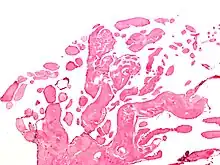

Micrograph of a papillary fibroelastoma, a benign tumor of heart valves. H&E stain. | |

- Papillary Fibroelastoma

A subset of the primary tumors of the heart are tumors that are found on the valves of the heart. Tumors that affect the valves of the heart are found in an equal distribution among the four heart valves.[2] The vast majority of these are papillary fibroelastomas. Primary tumors of the valves of the heart are more likely to occur in males. While most primary tumors of the valves of the heart are not malignant, they are more likely to have symptoms related to the valve, including neurologic symptoms and (in a few cases) sudden cardiac death.